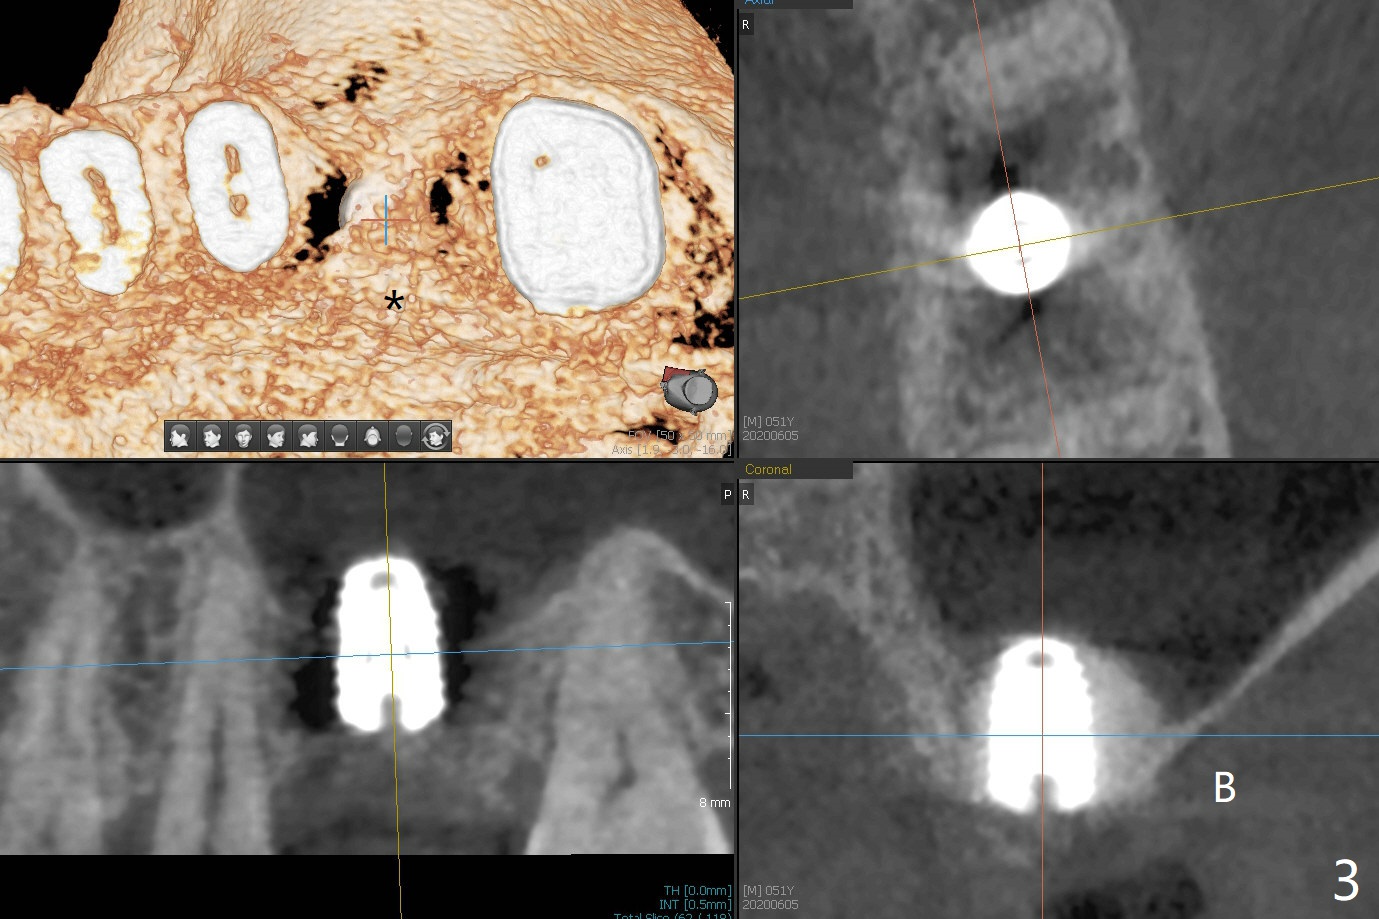

After using 4.5x5.3 mm and 3.5x7.3 mm drill at #14 with guide, the sinus floor is not perforated. When a 4.5x11 mm dummy implant is placed to the 2nd line (12 mm offset), the sinus membrane is perforated (Fig.1). A piece of PRF membrane and sticky bone are pushed into the sinus in an attempt for repair. A shorter implant is placed (5x7.3 (instead of 8.5) mm, Fig.2,3,5, as compared to Fig.3) to reduce postop sinus infection. In fact incision reveals palatal bony concavity. When the implant is placed, there is mild palatal thread exposure. With incision instead of tissue punch, it is easy to place bone graft over the small defect (Fig.3 *). The wound dehisces and heals 2 weeks postop (Fig.6). There is bone loss 6.5 months postop (Fig.7 *), corresponding to palatal thread exposure. After decortication and periosteal underscoring, cortical allograft mixed with ~.25 cc GEM21S is placed (Fig.8 *).